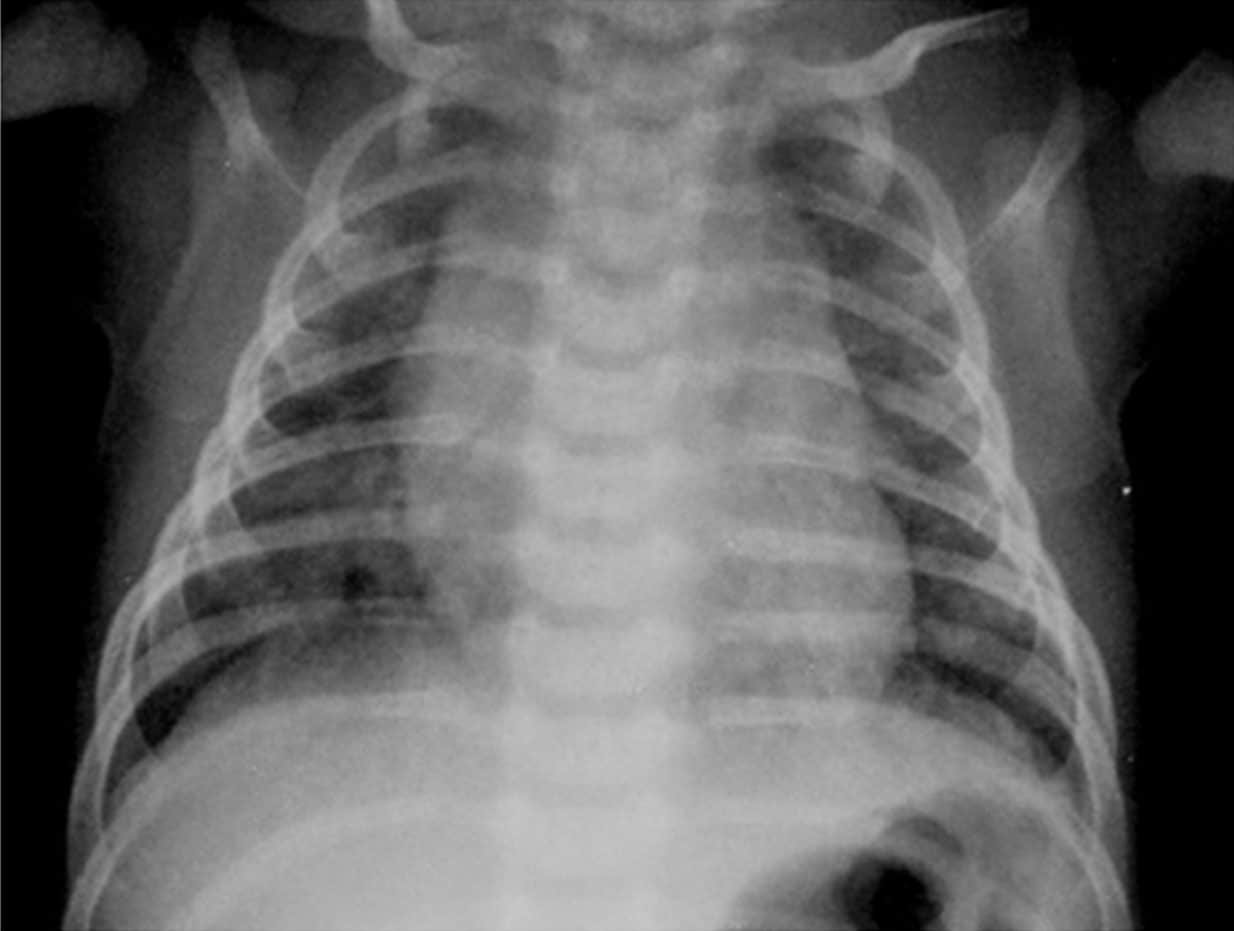

Measles patient with a complication of respiratory failure

Infants, pregnant women, and malnourished children with impaired immune systems are most likely to have complications from measles. The most frequent complication is pneumonia, which can be brought on by a subsequent bacterial infection or the measles virus (Hecht giant cell pneumonia).

Croup, otitis media, and diarrhea from secondary infections are some additional complications. Measles keratoconjunctivitis, which can result in blindness, most frequently affects young children with vitamin A deficiency.